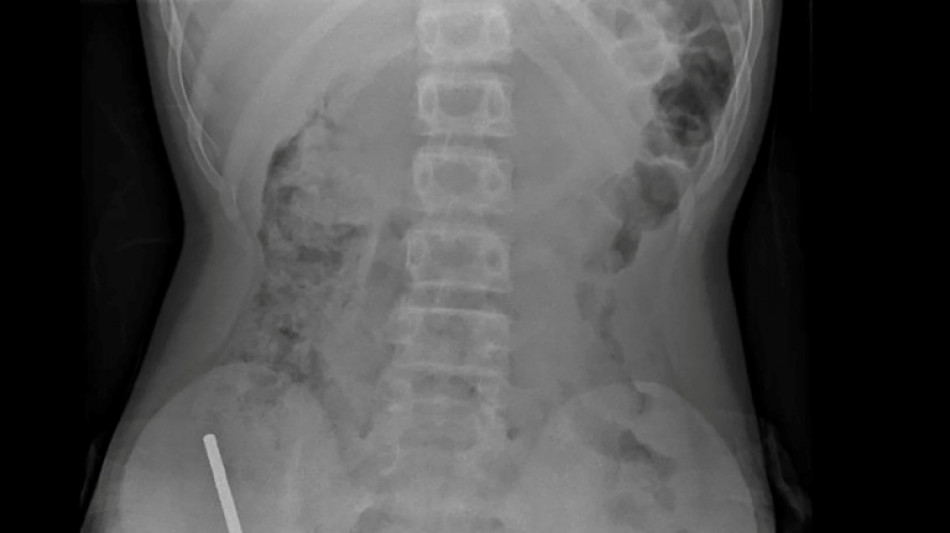

Nouvelle-Zélande: un adolescent opéré après avoir ingéré près de 100 aimants achetés sur Temu

En Nouvelle-Zélande, un adolescent de 13 ans s'est vu retirer plusieurs parties nécrosées de ses intestins après avoir avalé près d'une centaine d'aimants achetés en ligne sur le site Temu, a rapporté vendredi une revue médicale.

Après avoir souffert de douleurs abdominales pendant quatre jours, l'adolescent a été transporté à l'hôpital de Tauranga, sur l'île du Nord.

"Il avoué avoir ingéré entre 80 et 100 aimants puissants au néodyme, de 5x2mm environ, une semaine plus tôt", indique un rapport des médecins de l'hôpital de cet hôpital, publié dans le New Zealand Medical Journal (NZMJ).

Ce type d'aimants, interdit en Nouvelle-Zélande depuis janvier 2013, aurait été acheté sur la plateforme chinoise d'e-commerce Temu.

Les médecins ont déclaré que la pression exercée par les aimants avait provoqué une nécrose dans quatre zones de l'intestin grêle et du gros intestin du garçon.

Il a été opéré afin que l'on lui retire les aimants et les tissus nécrosés, et il a pu rentrer chez lui après huit jours à l'hôpital.

L'article explique qu'une intervention chirurgicale à la suite de l'ingestion d'aimants peut entraîner des complications, telles qu'une obstruction intestinale, une hernie abdominale et des douleurs chroniques.